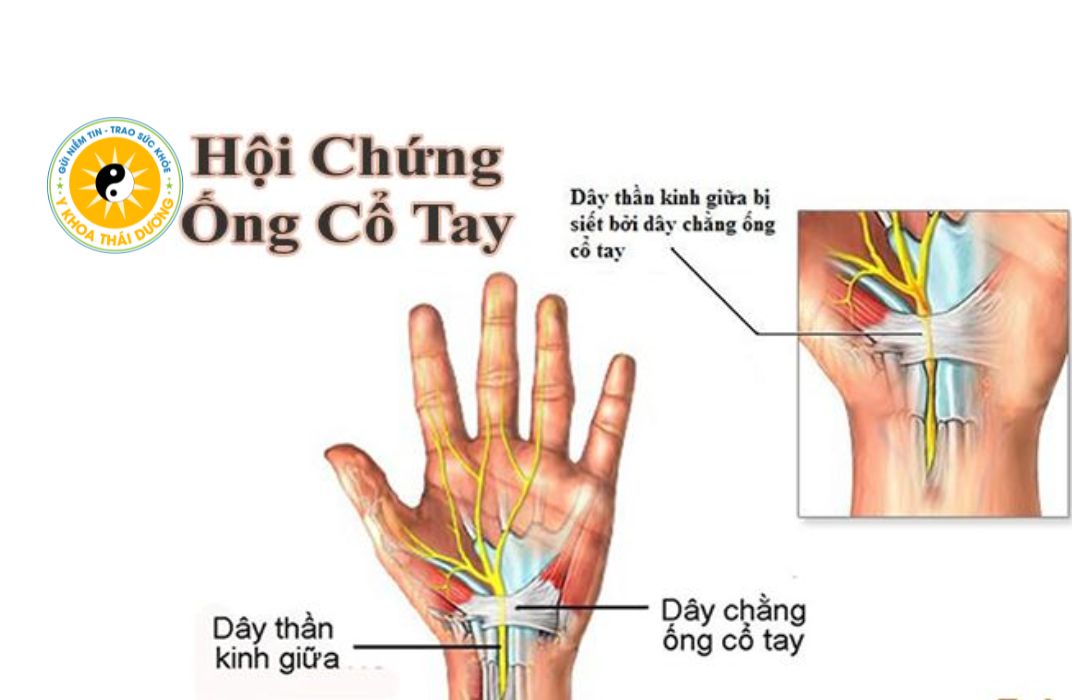

Hội chứng ống cổ tay là gì? Dấu hiệu nhận biết sớm và mức độ nguy hiểm

Hội chứng ống cổ tay (Carpal Tunnel Syndrome) là bệnh lý thần kinh phổ biến,...

Hội chứng ống cổ tay ở nhân viên văn phòng: Nguyên nhân và cách phòng ngừa

Hội chứng ống cổ tay ở nhân viên văn phòng (Carpal Tunnel Syndrome – CTS)...